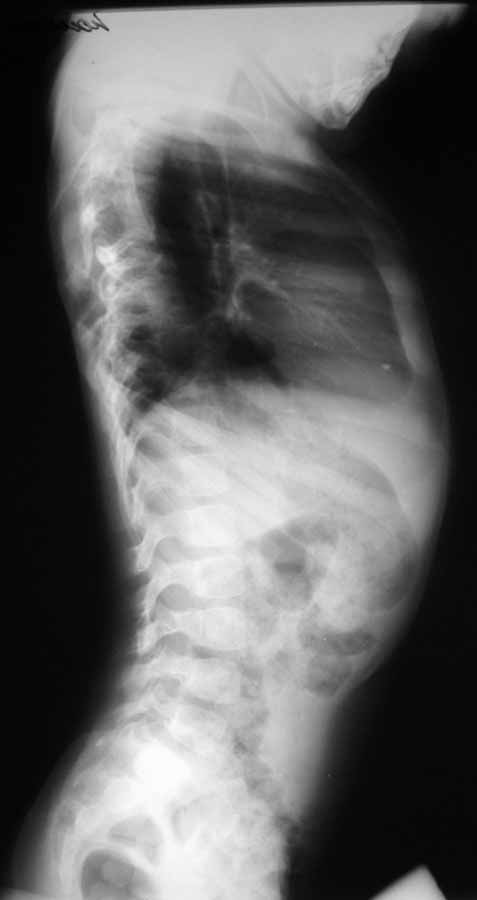

Уважаемые коллеги!Выскажите, пожалуйста, мнения о тактике лечения данной пациентки. Девочка, 5 лет. ДЗ: Врожденный S–образный сколиоз, аномалия развития позвоночника: клиновидные 5–6 грудные позвонки, аномалия развития грудной клетки: деформация ребер. Анамнез заболевания: Болеет с рождения, начала ходить в 1,5 года. В 5 месяцев мама отметила наличие реберного горба, который увеличивался в размерах, в 1год 10 месяцев – произведена рентгенография позвоночника – отмечена его деформация. Заранее благодарю! С уважением, А.В.Владзимирский

Рентгенограмма

spine2.JPG